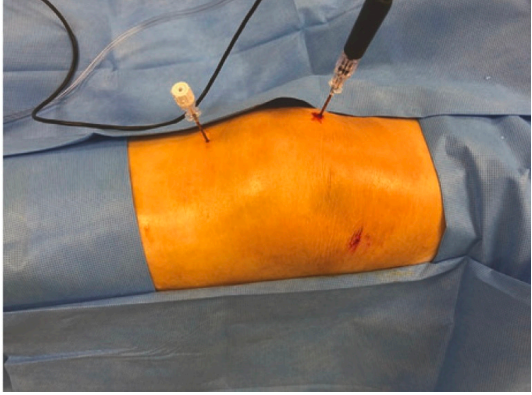

The procedure is done in operation theatre under local anesthesia. The patient is made to lie on the operation table and the appropriate joint/ spine is identified under imaging guidance. RF needle is inserted under imaging guidance to target the concerned nerve and thereafter RFA is performed using RF machine

All of these procedures take less than 1 hour. After the procedure is over the patient is shifted to recovery room and monitored for any postoperative complications/ drug reactions for 2 hours.

Knee joint

- RFA genicular nerve